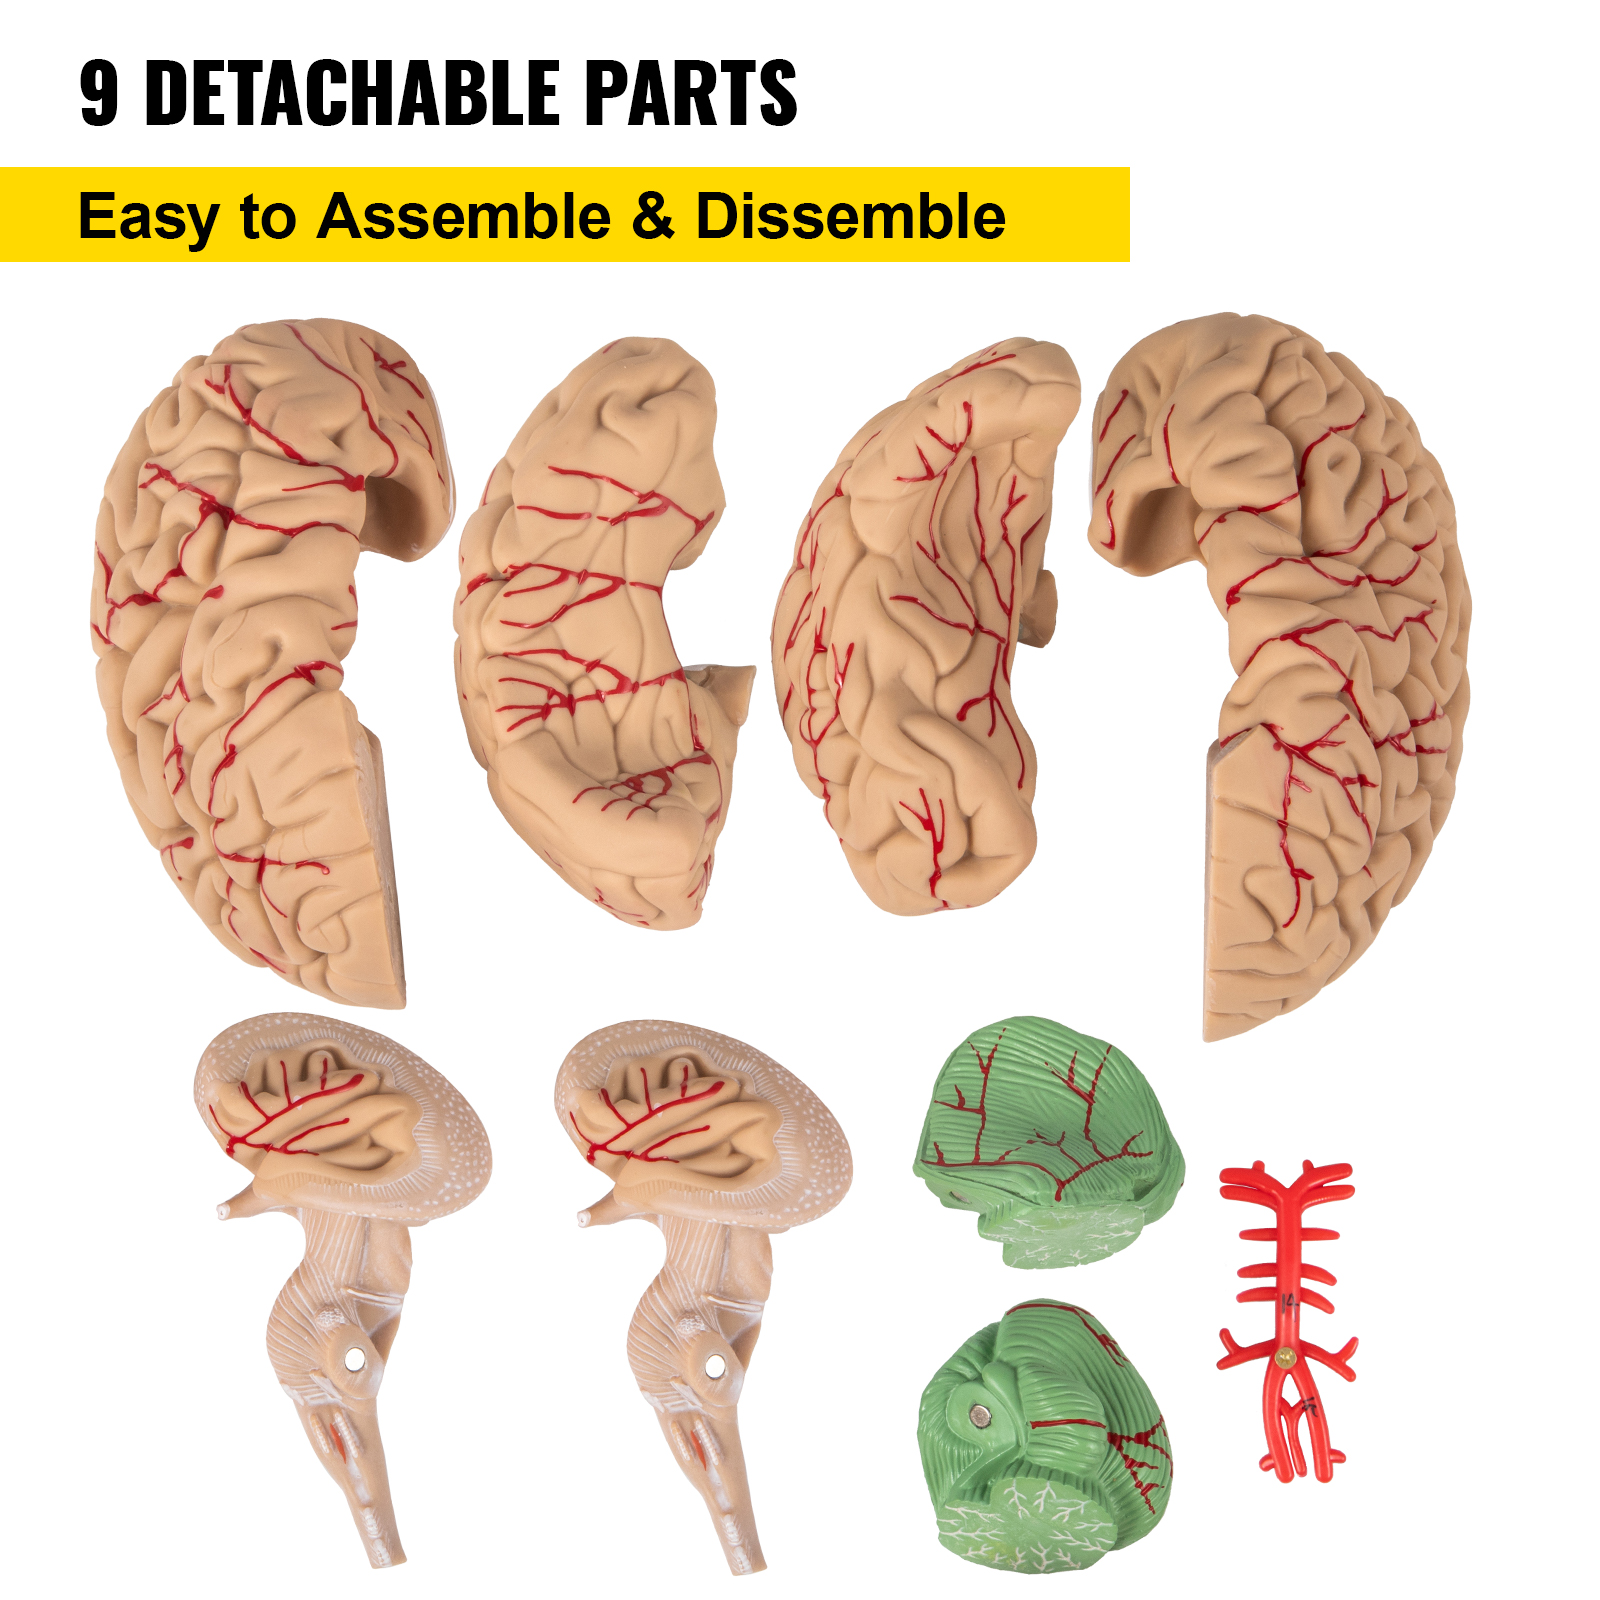

9 Detachable Parts

The model can be divided into nine parts and is easy to assemble and disassemble. The users can observe the brain's internal structure from all angles to better learn and understand the functions and structure of the human brain.

9 Detachable Parts

The model can be divided into nine parts and is easy to assemble and disassemble. The users can observe the brain's internal structure from all angles to better learn and understand the functions and structure of the human brain.